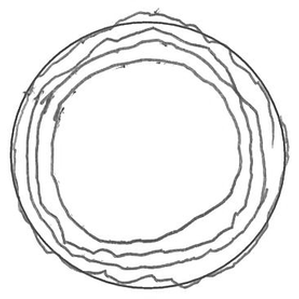

TASK_04: Trace Circle

Healthy Control

Alzheimer's

Real handwriting samples across 6 different tasks showing motor control and cognitive differences between healthy controls and Alzheimer's patients